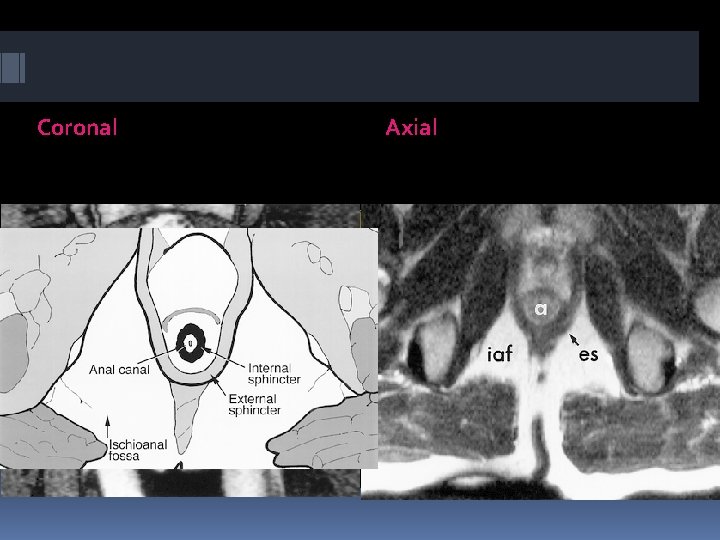

On axial and coronal MR images , the different layers of anal sphincter and the surrounding structures can be displayed perfectly

Coronal Axial